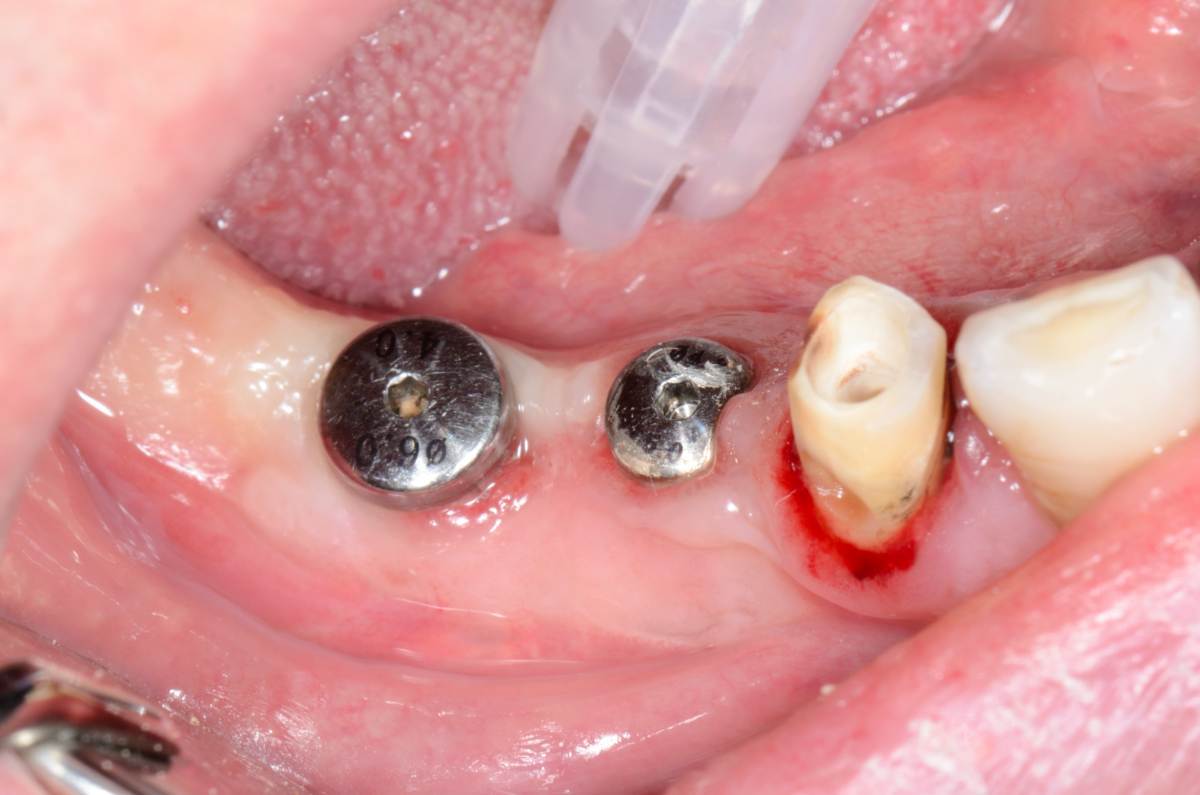

Fin Опубликовано 18 апреля, 2025 Поделиться Опубликовано 18 апреля, 2025 Ранее установил 2 Импланта необиотек. Пришло время создать кератенизированную слизистую вокруг имплантатов. Решил попробовать СДТ с неба по Едранову. Припинили при помощи безударных пинов. Через 2 недели пины удалены. Через полтора месяца открыл и подсадил ССТ щёчно и у 4.5 язычно дополнительно. Еще через месяц провел протезирование коронками из ДЦ заодно поменял коронку на 4.4. Сейчас активнот использую эту методику и нравится больше классического СДТ на надкостницу. В моих руках работает лучше и быстрее. Заметил что СДТ приживается до уровня пинов, начал ставить их чуть ниже. 3 1 1 Ссылка на комментарий